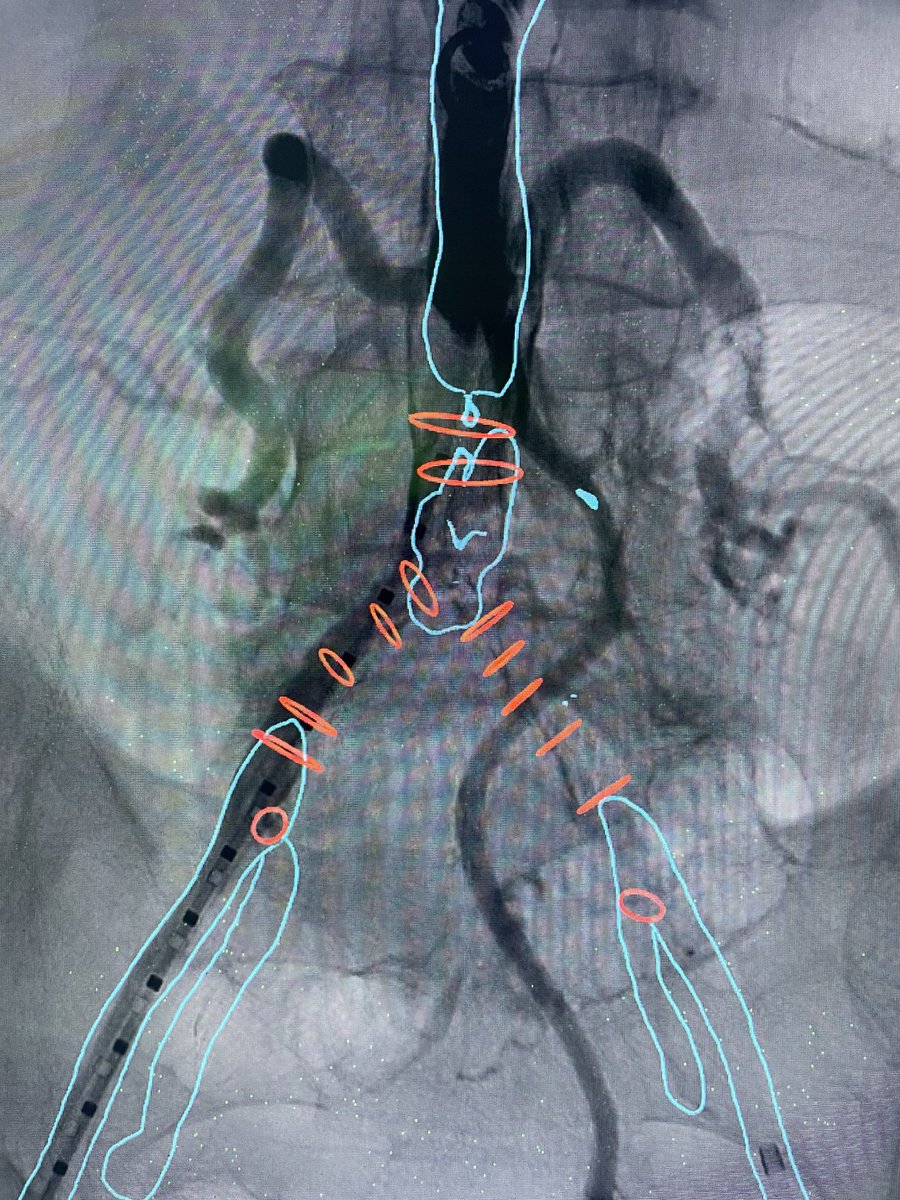

Listening to "Het aneurysma van de aorta abdominalis (AAA) met Patrick Vriens en Jan Heyligers" at methetmesaantafel.buzzsprout.com/1019002/120991…